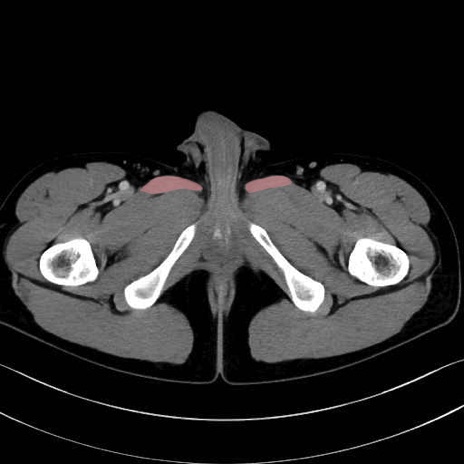

長内転筋(Adductor longus muscle)のCT画像の解剖

長内転筋 (Adductor longus)